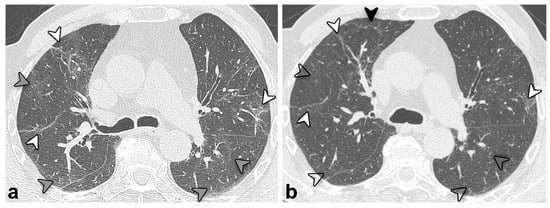

| Type of CT pattern | 0.038 | ||

| GGO | 8 (16) | 2 (4) | |

| Reticular | 31 (63) | 38 (79) | |

| Combined | 10 (21) | 8 (17) | |

| Consolidation | 2 (4) | 2 (4) | 1.000 |

| Architectural distortion | 45 (92) | 46 (96) | 1.000 |

| Bronchial dilatation | 44 (90) | 42 (88) | 0.683 |

| Distribution | |||

| Bilateral | 47 (96) | 48 (100) | NA ** |

| Axial distribution (central/peripheral/neither) | 1 (2)/18 (37)/30 (61) | 0 (0)/28 (58)/20 (42) | NA ** |

| Cranio-caudal distribution (superior/medium/inferior/none) | 2 (4)/1 (2)/7 (14)/39 (80) | 1 (2)/6 (13)/12 (25)/29 (60) | 0.047 |